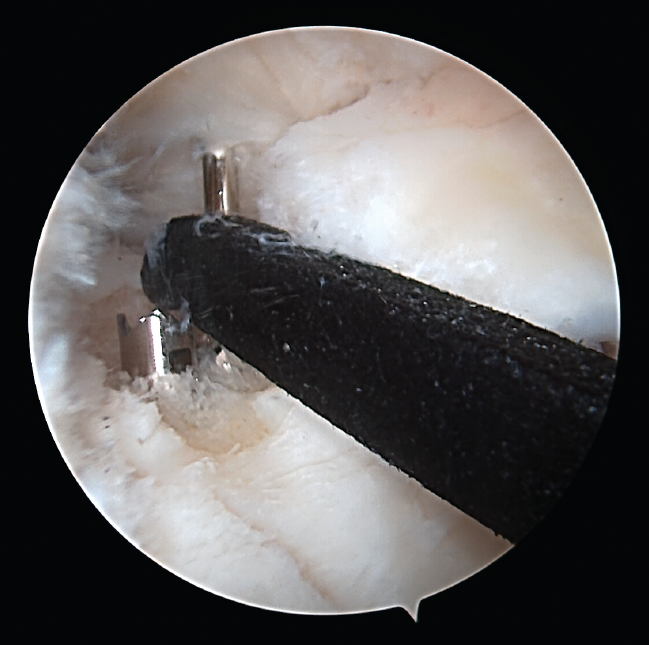

Standard anteromedial and anterolateral portals were used. Once the rupture was identified, the bed of the meniscal root was prepared with an arthroscopic drill, removing the cartilage and leaving a freshened bone base. Using the corresponding guides (Figure 5), two 2.8-mm tunnels were made for passing two number 2 FiberStick® sutures (Arthrex, Inc., Naples, Florida, USA) through one of them. After suturing the meniscus with two simple stitches using a FirstPass® suture passer (Smith & Nephew, Inc., Massachusetts, USA), they were recovered through the other tunnel and knotted onto themselves at the anterior cortical layer of the tibia.

Figure 5. Adaptation of the guide in the surgical field.

One of the patients in the standard guide group required modification of the perforation secondary to intraarticular exit of the Kirschner wire in a position different from that planned, due to positioning difficulties caused by the existence of a narrow intercondylar groove and prominent spines. The 3D printed guides adapted on both supports to the bone surface of the tibia and were precise in conducting the guide needles towards the planned position (Figures 6 and 7). There were no problems derived from friction between the metal of the needles and the bore of the customized guide, and handling was ergonomically satisfactory for the surgeon.